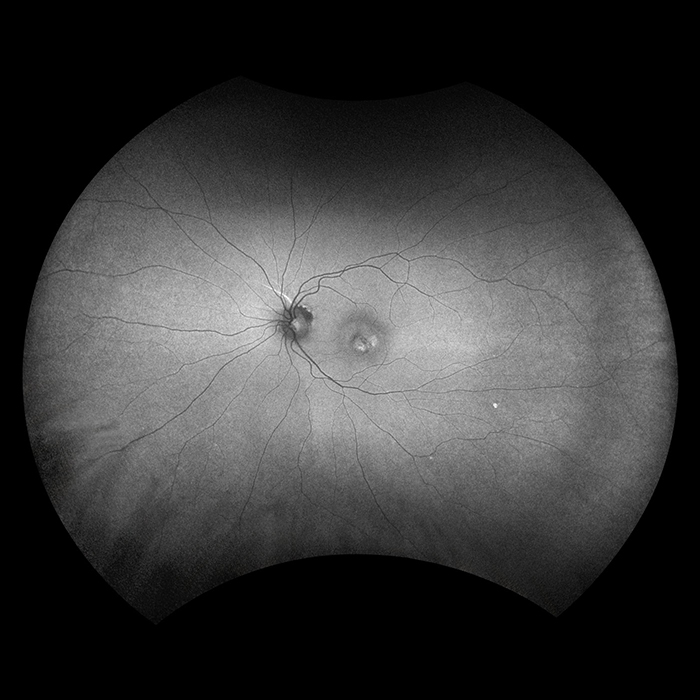

A non-invasive technique, autofluorescence was developed over the last decade to study the fluorescent properties of lipofuscin, which is a mixture of autofluorescent pigments that accumulate in the retinal pigment epithelium as a byproduct from the incomplete degradation of photoreceptor outer segments. AF imaging gives information over and above conventional imaging techniques such as fundus photos or fluorescence angiography as it allows visualization of the metabolic changes at the level of the RPE and helps to identify areas that may be at high risk for the development of geographic atrophy or CNV.